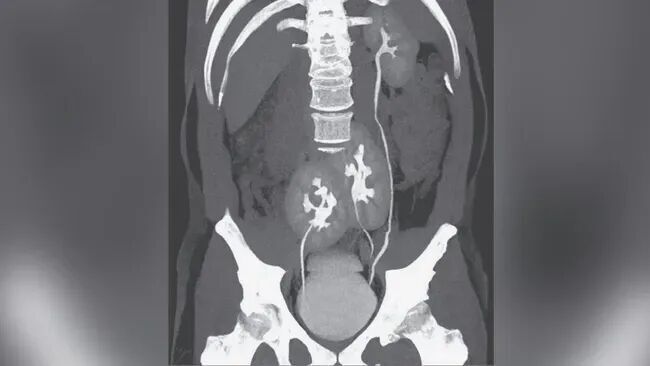

需要指出的是,突出肾在剖解结构上具有一定各种性。有些东说念主的第三个肾脏不错透顶零丁存在,也可能仅通过一层薄薄的组织与左近肾脏承接,功能上亦可能闲居或存在各别。类似的未必发现并非个例。举例,《新英格兰医学杂志》(NEJM)曾在 2020 年报说念,别称巴西男性因椎间盘凸起导致腰痛就医,在进行 CT 检查时无意发现体内存在第三个肾脏。该突出肾位于骨盆隔邻,并与右侧肾脏承接,但三个肾脏均功能闲居,也未被以为是激励其症状的平直原因。

患者的三颗肾脏:右上为外不雅闲居的肾脏,另有两颗肾脏在骨盆处承接。开始:NEJM